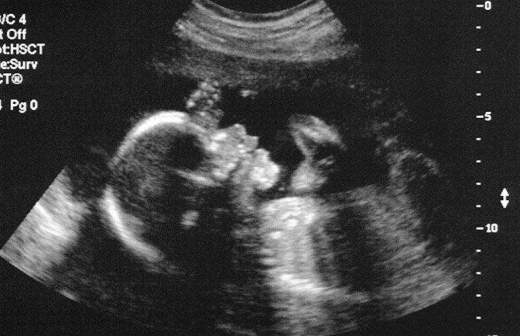

Москвичка, которой диагностировали врожденную аномалию матки, родила двух здоровых близнецов. Об этом рассказала завотдела патологии беременности ГКБ №  29 им. Н. Э. Баумана Ольга Лукановская.

Ранее у женщины обнаружили патологию  репродуктивного органа — матка раздвоилась и приняла форму сердца. Медики назвали рождение близнецов чудом.

Эмбрионы развивались в левой и правой половинах матки, которая приняла форму сердца. Поэтому впервые единоутробные сестра и брат встретились только после рождения.